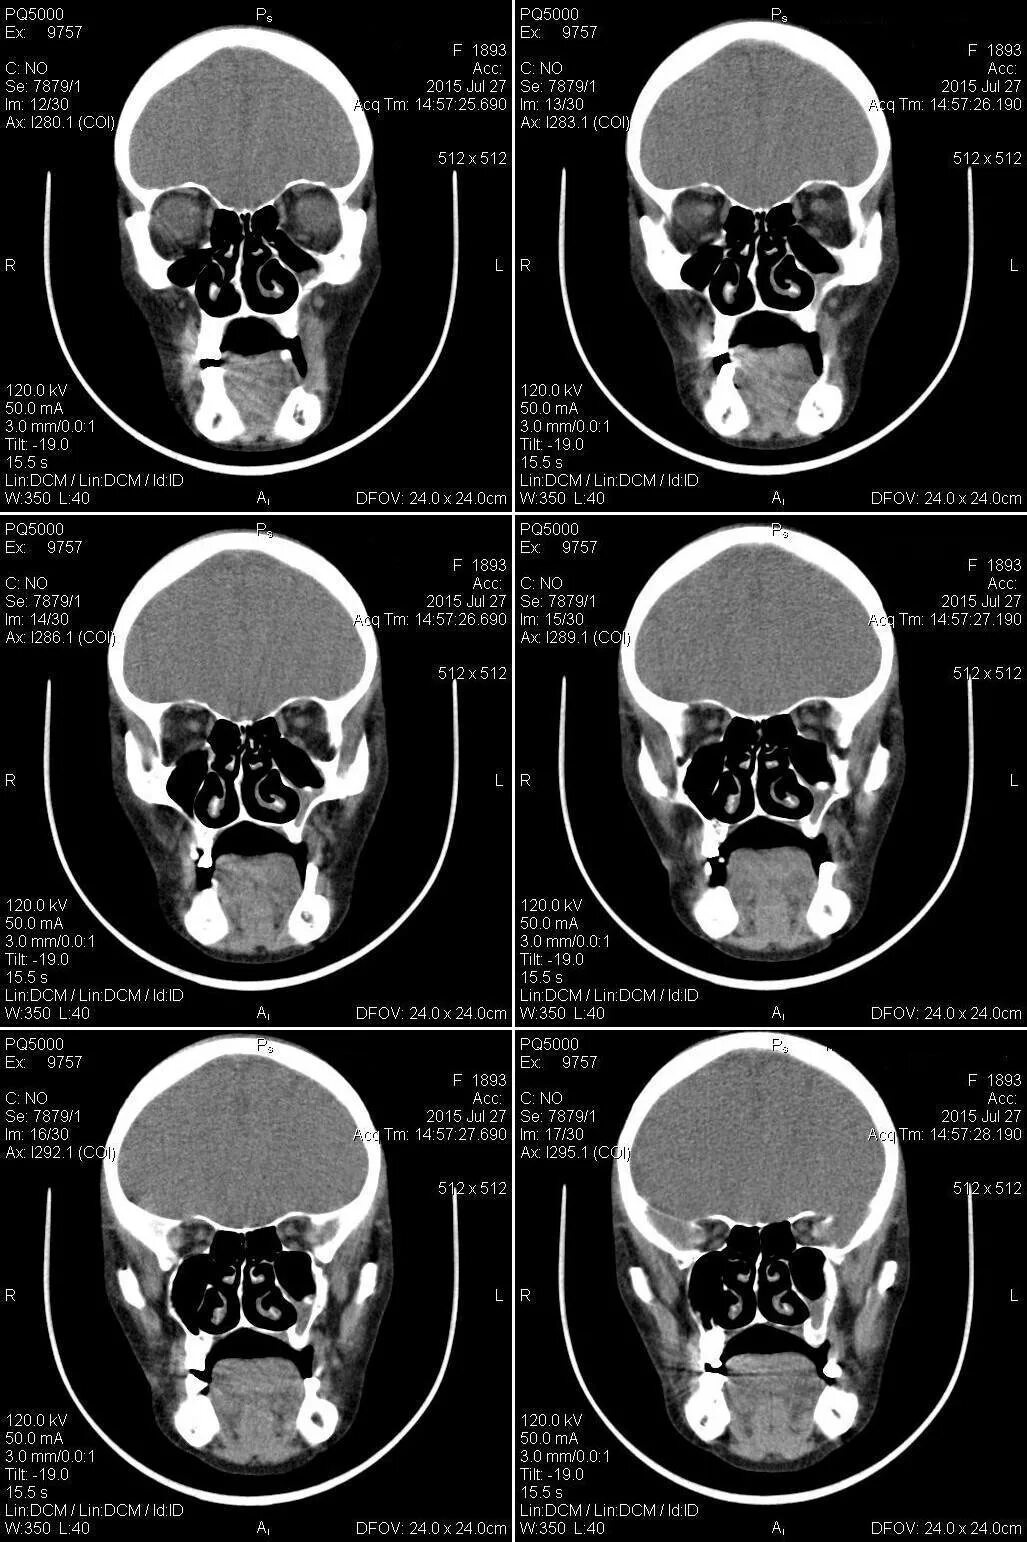

Сфеноидит симптомы